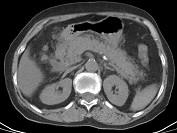

问题 男,30岁,上腹部剧痛,恶心呕吐,压痛反跳痛,血细胞计数升高,血和尿淀粉酶升高,影像表现如图,最可能的诊断是什么 ( )

选项 A、急性胰腺炎 B、慢性胰腺炎 C、胃溃疡穿孔 D、胰腺癌 E、急性肠梗阻

答案 A